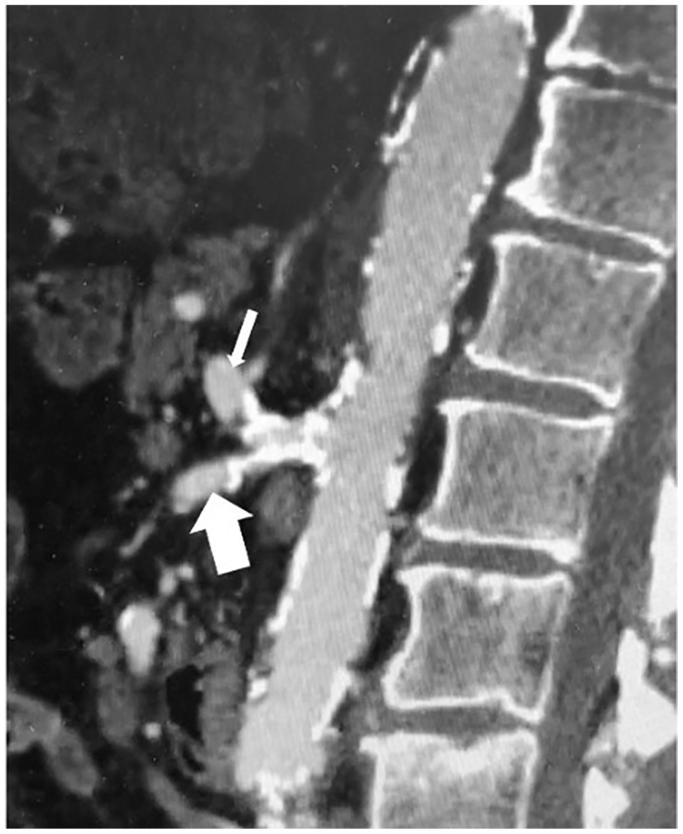

The celiacomesenteric trunk (CMT) is a rare anatomical variant where the celiac axis and superior mesenteric artery share a common origin. Despite its rarity, CMT has significant implications across various medical fields, particularly in surgical planning and interventional procedures. We report a case of chronic mesenteric ischemia owing to atherosclerotic stenosis at the CMT bifurcation, necessitating a complex interventional approach. Kissing covered stent angioplasty was successfully performed, resulting in revascularization, symptom resolution, and no restenosis at 1-year follow-up. This report highlights the feasibility and effectiveness of the kissing stent technique in managing complex CMT bifurcation obstructions in patients with chronic mesenteric ischemia.

腹腔肠系膜干(CMT)是一种罕见的解剖变异,即腹腔干和肠系膜上动脉有共同的起源。尽管CMT罕见,但它在各个医学领域都有重要意义,尤其是在手术规划和介入操作方面。我们报告一例因CMT分叉处动脉粥样硬化狭窄导致的慢性肠系膜缺血病例,需要采用复杂的介入方法。成功实施了吻合法覆膜支架血管成形术,实现了血管再通、症状缓解,且在1年随访时无再狭窄。本报告强调了吻合法支架技术在处理慢性肠系膜缺血患者复杂CMT分叉处梗阻方面的可行性和有效性。